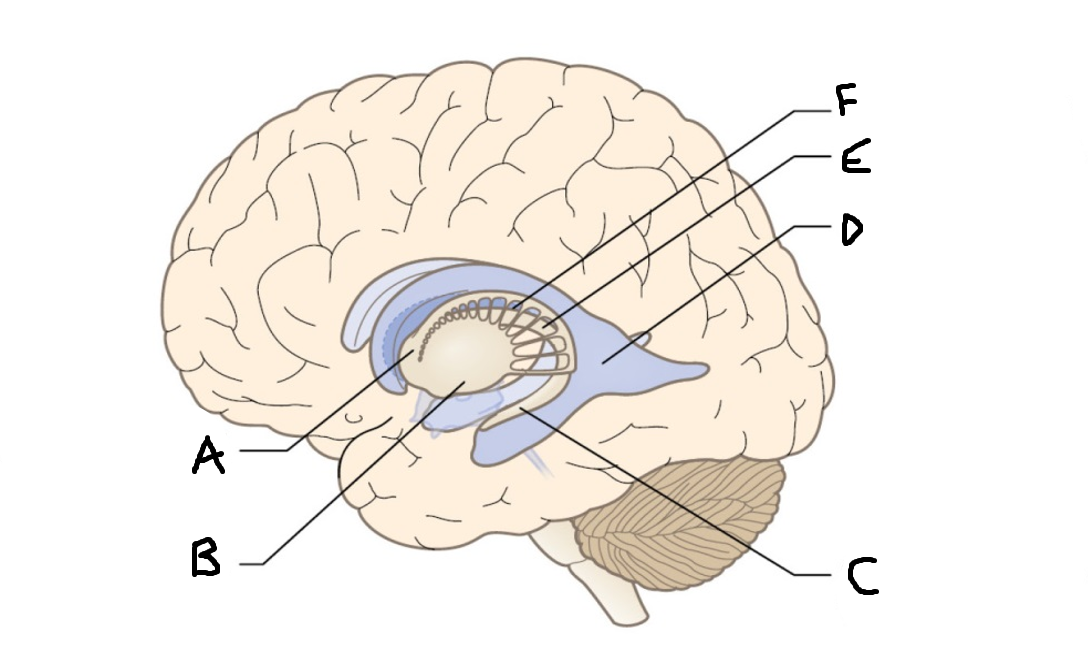

caudate nucleus head

A

Putamen

B

caudate nucleus tail

C

Lateral ventricle

D

caudate nucleus body

E

internal capsule

F